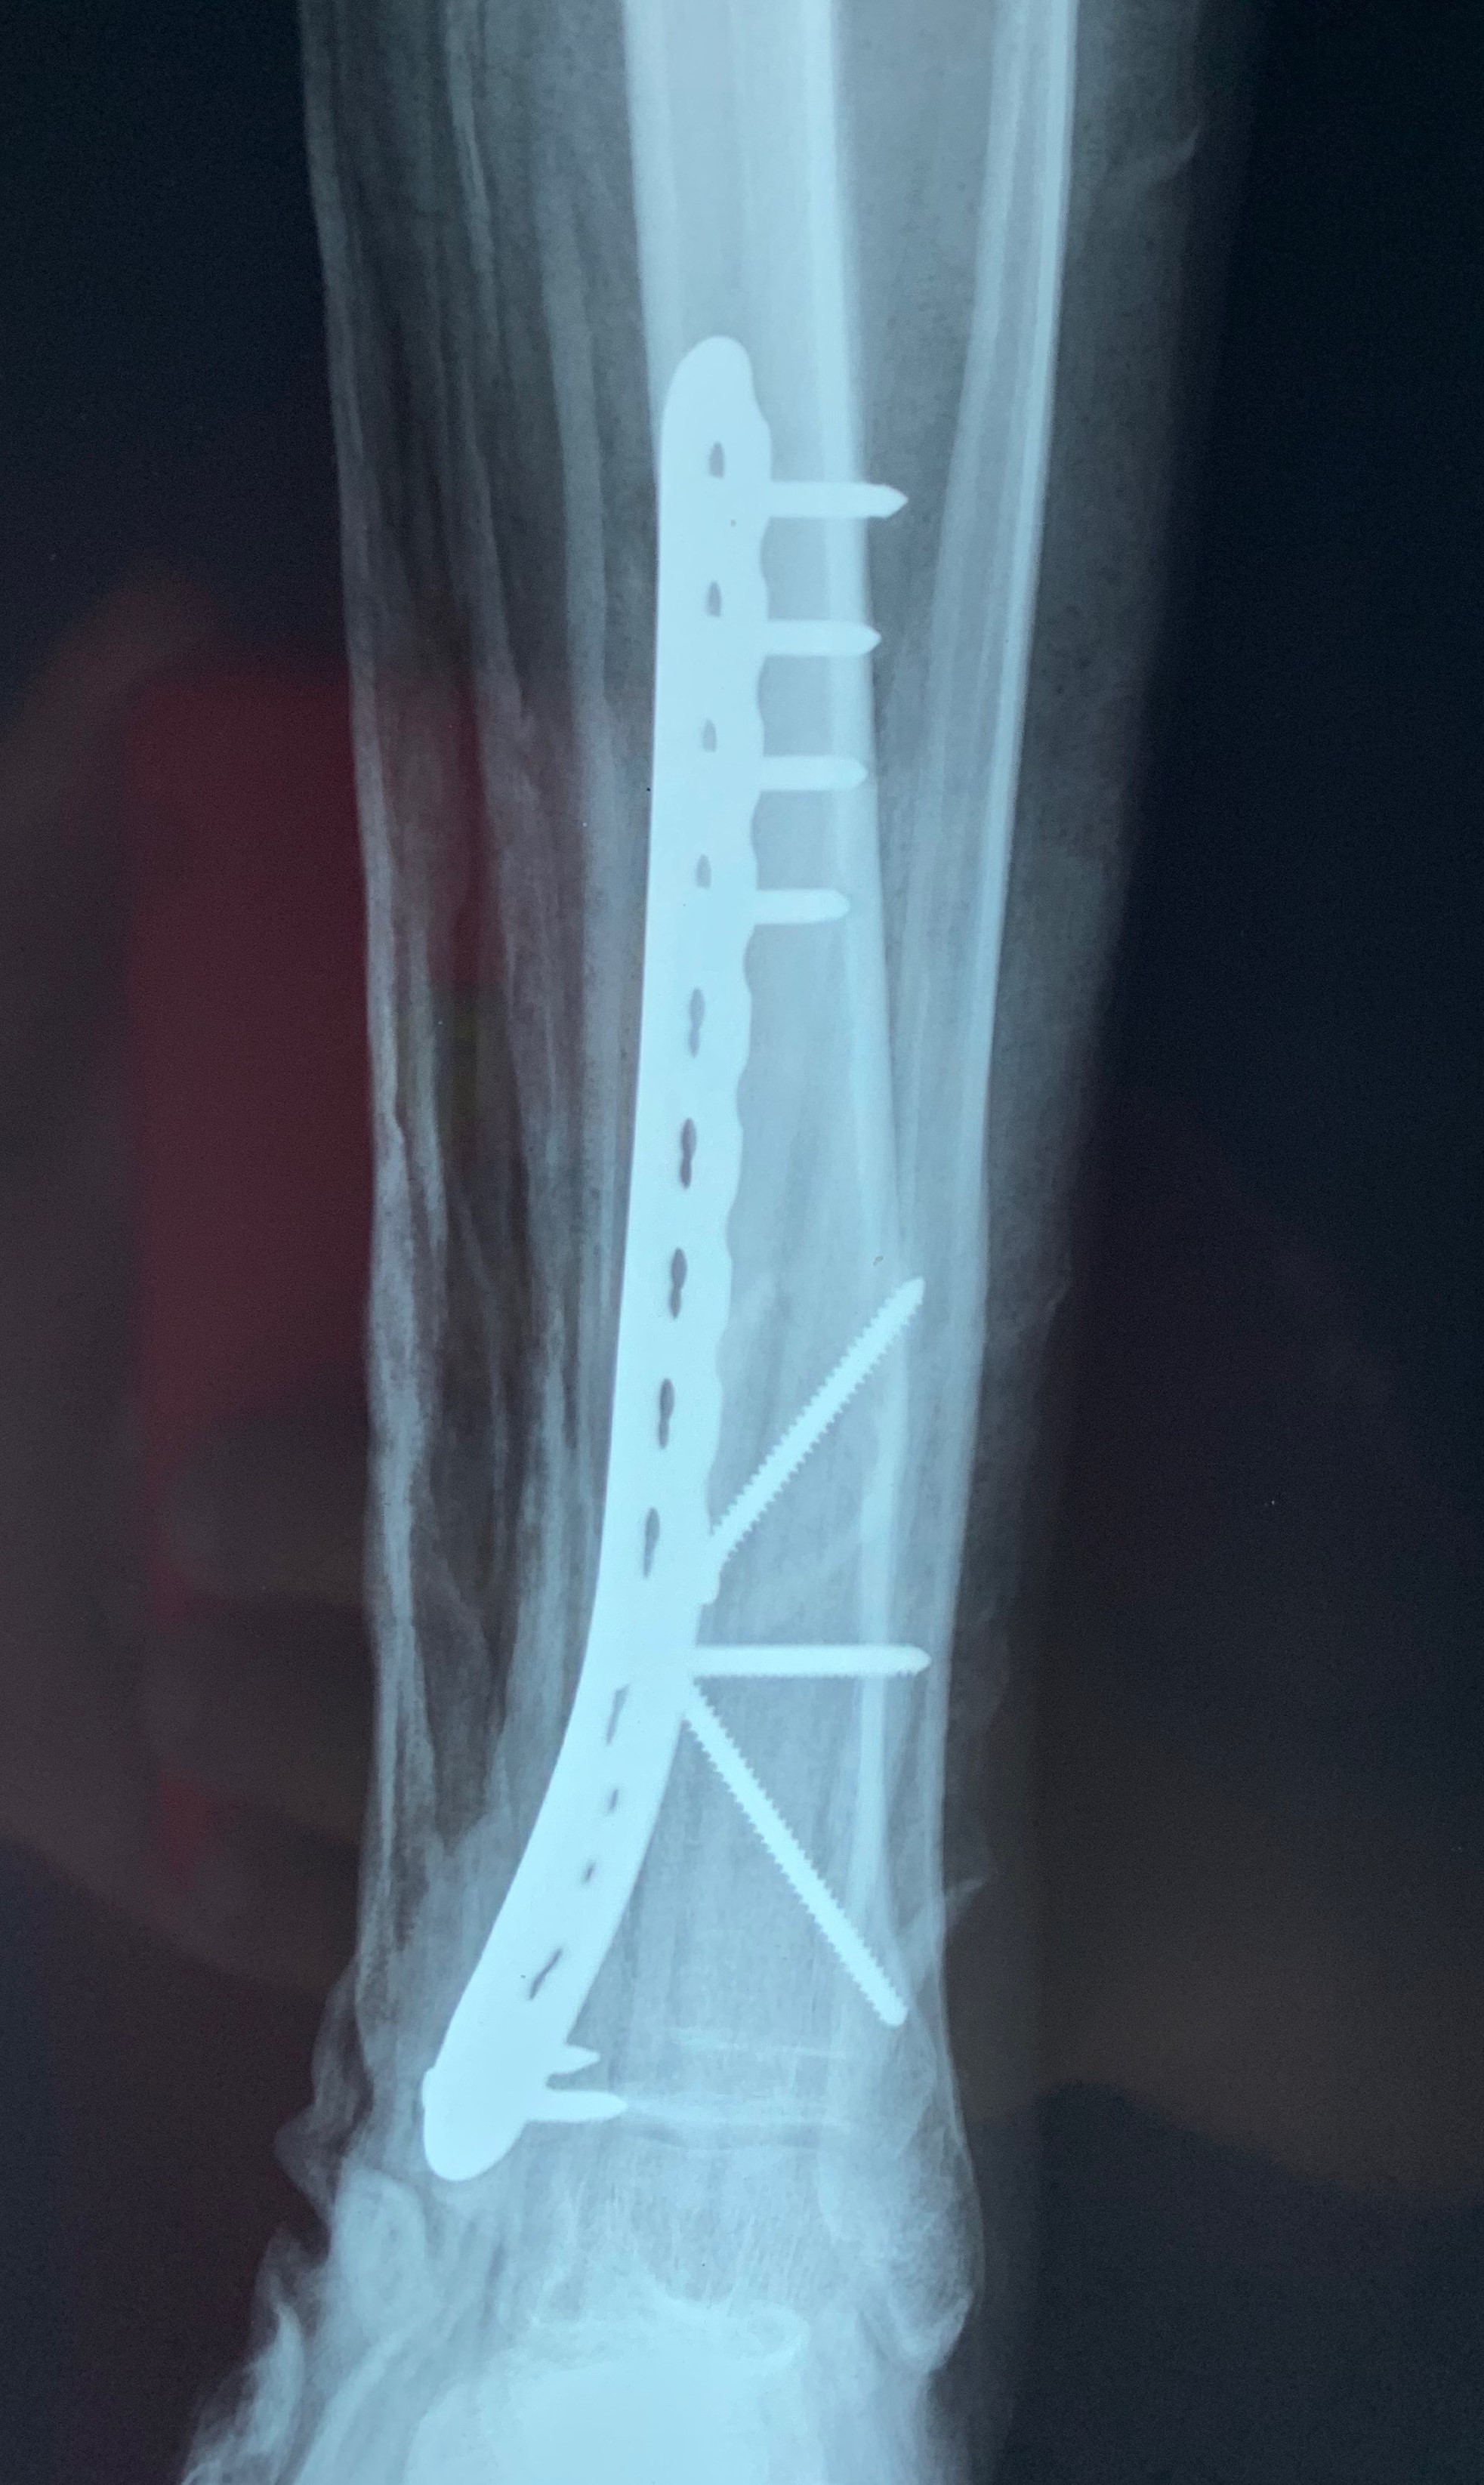

CRIF WITH MIPPO

A 25 year old male case of post-traumatic left-sided distal one-third tibia spiral oblique fracture with a butterfly fragment was treated.

Surgery performed was closed reduction & internal fixation with minimally invasive percutaneous plate osteosynthesis.